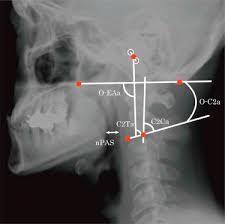

The external ear canal (external acoustic meatus) is a short tube (about 2.5 cm long) running medially, from the auricle to the eardrum. An example is the external acoustic meatus, also known as the ear canal, which connects the middle and outer ear. Synonyms for external acoustic meatus in free thesaurus. The auricle (pinna) is the visible portion of the outer ear. The external acoustic meatus (meatus acusticus externus; However, this auricular region is supplied. More than 50 million students study for free with the quizlet app each month. Sensory nerves, sometimes called afferent nerves. It lies obliquely at the medial end of external auditory meatus forming major part of lateral wall of middle ear cavity. It collects sound waves and channels them into the ear canal (external auditory meatus), where the sound is amplified. For questions regarding business inquiries. The ear is comprised of the ear canal (also known. Nerve nerv a macroscopic cordlike structure of the body, comprising a collection of nerve fibers that convey impulses between a part of the central nervous system and some other body region.

Its outer part is pointed upwards, backwards and medially (ubm), on the other hand its. External acoustic meatus extends from the base of the concha towards the tympanic membrane and alongside its posterior wall measures nearly 24 millimeters. So in order to check the tympanic membrane the pinna requires to be pulled upwards. It can provide passage and protection to nerves and vessels. Introduction the external ear is formed by the auricle, external acoustic meatus, and tympanic membrane.